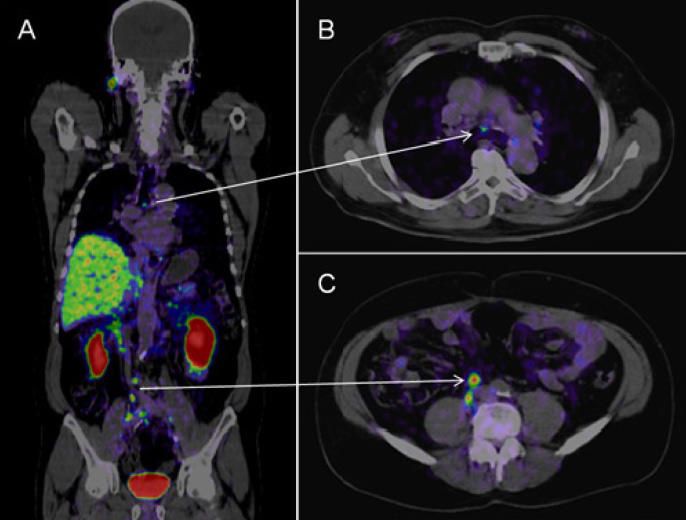

What lesion is indicated by the arrows?

PSMA PET is highly robust in identifying prostate cancer lesions which are otherwise deemed unremarkable.